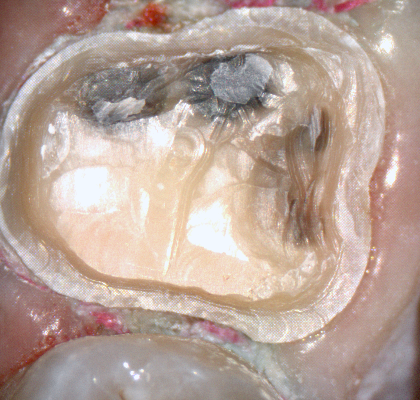

The following pictures depict the sequence of burs we recommend that you use to finish a preparation quickly. While patient is getting numb, take a quick look at the clearance you will need to reach proper material thickness. Once the quadrant is isolated with isolite and optragate, take an occlusal router bur and create a trough to gain the proper depth. Follow that with a flat disk, and you can quickly reduce the occlusal height.

A shoulder bur of .8 mm thickness can help you reduce the interproximal areas as well as the buccal and lingual margin lines. Before finishing the prep, place hemostatic agent like expasyl in the sulcus and place retraction cord. while it is setting, check your reduction. If you need more space, now is the time to reduce some more.